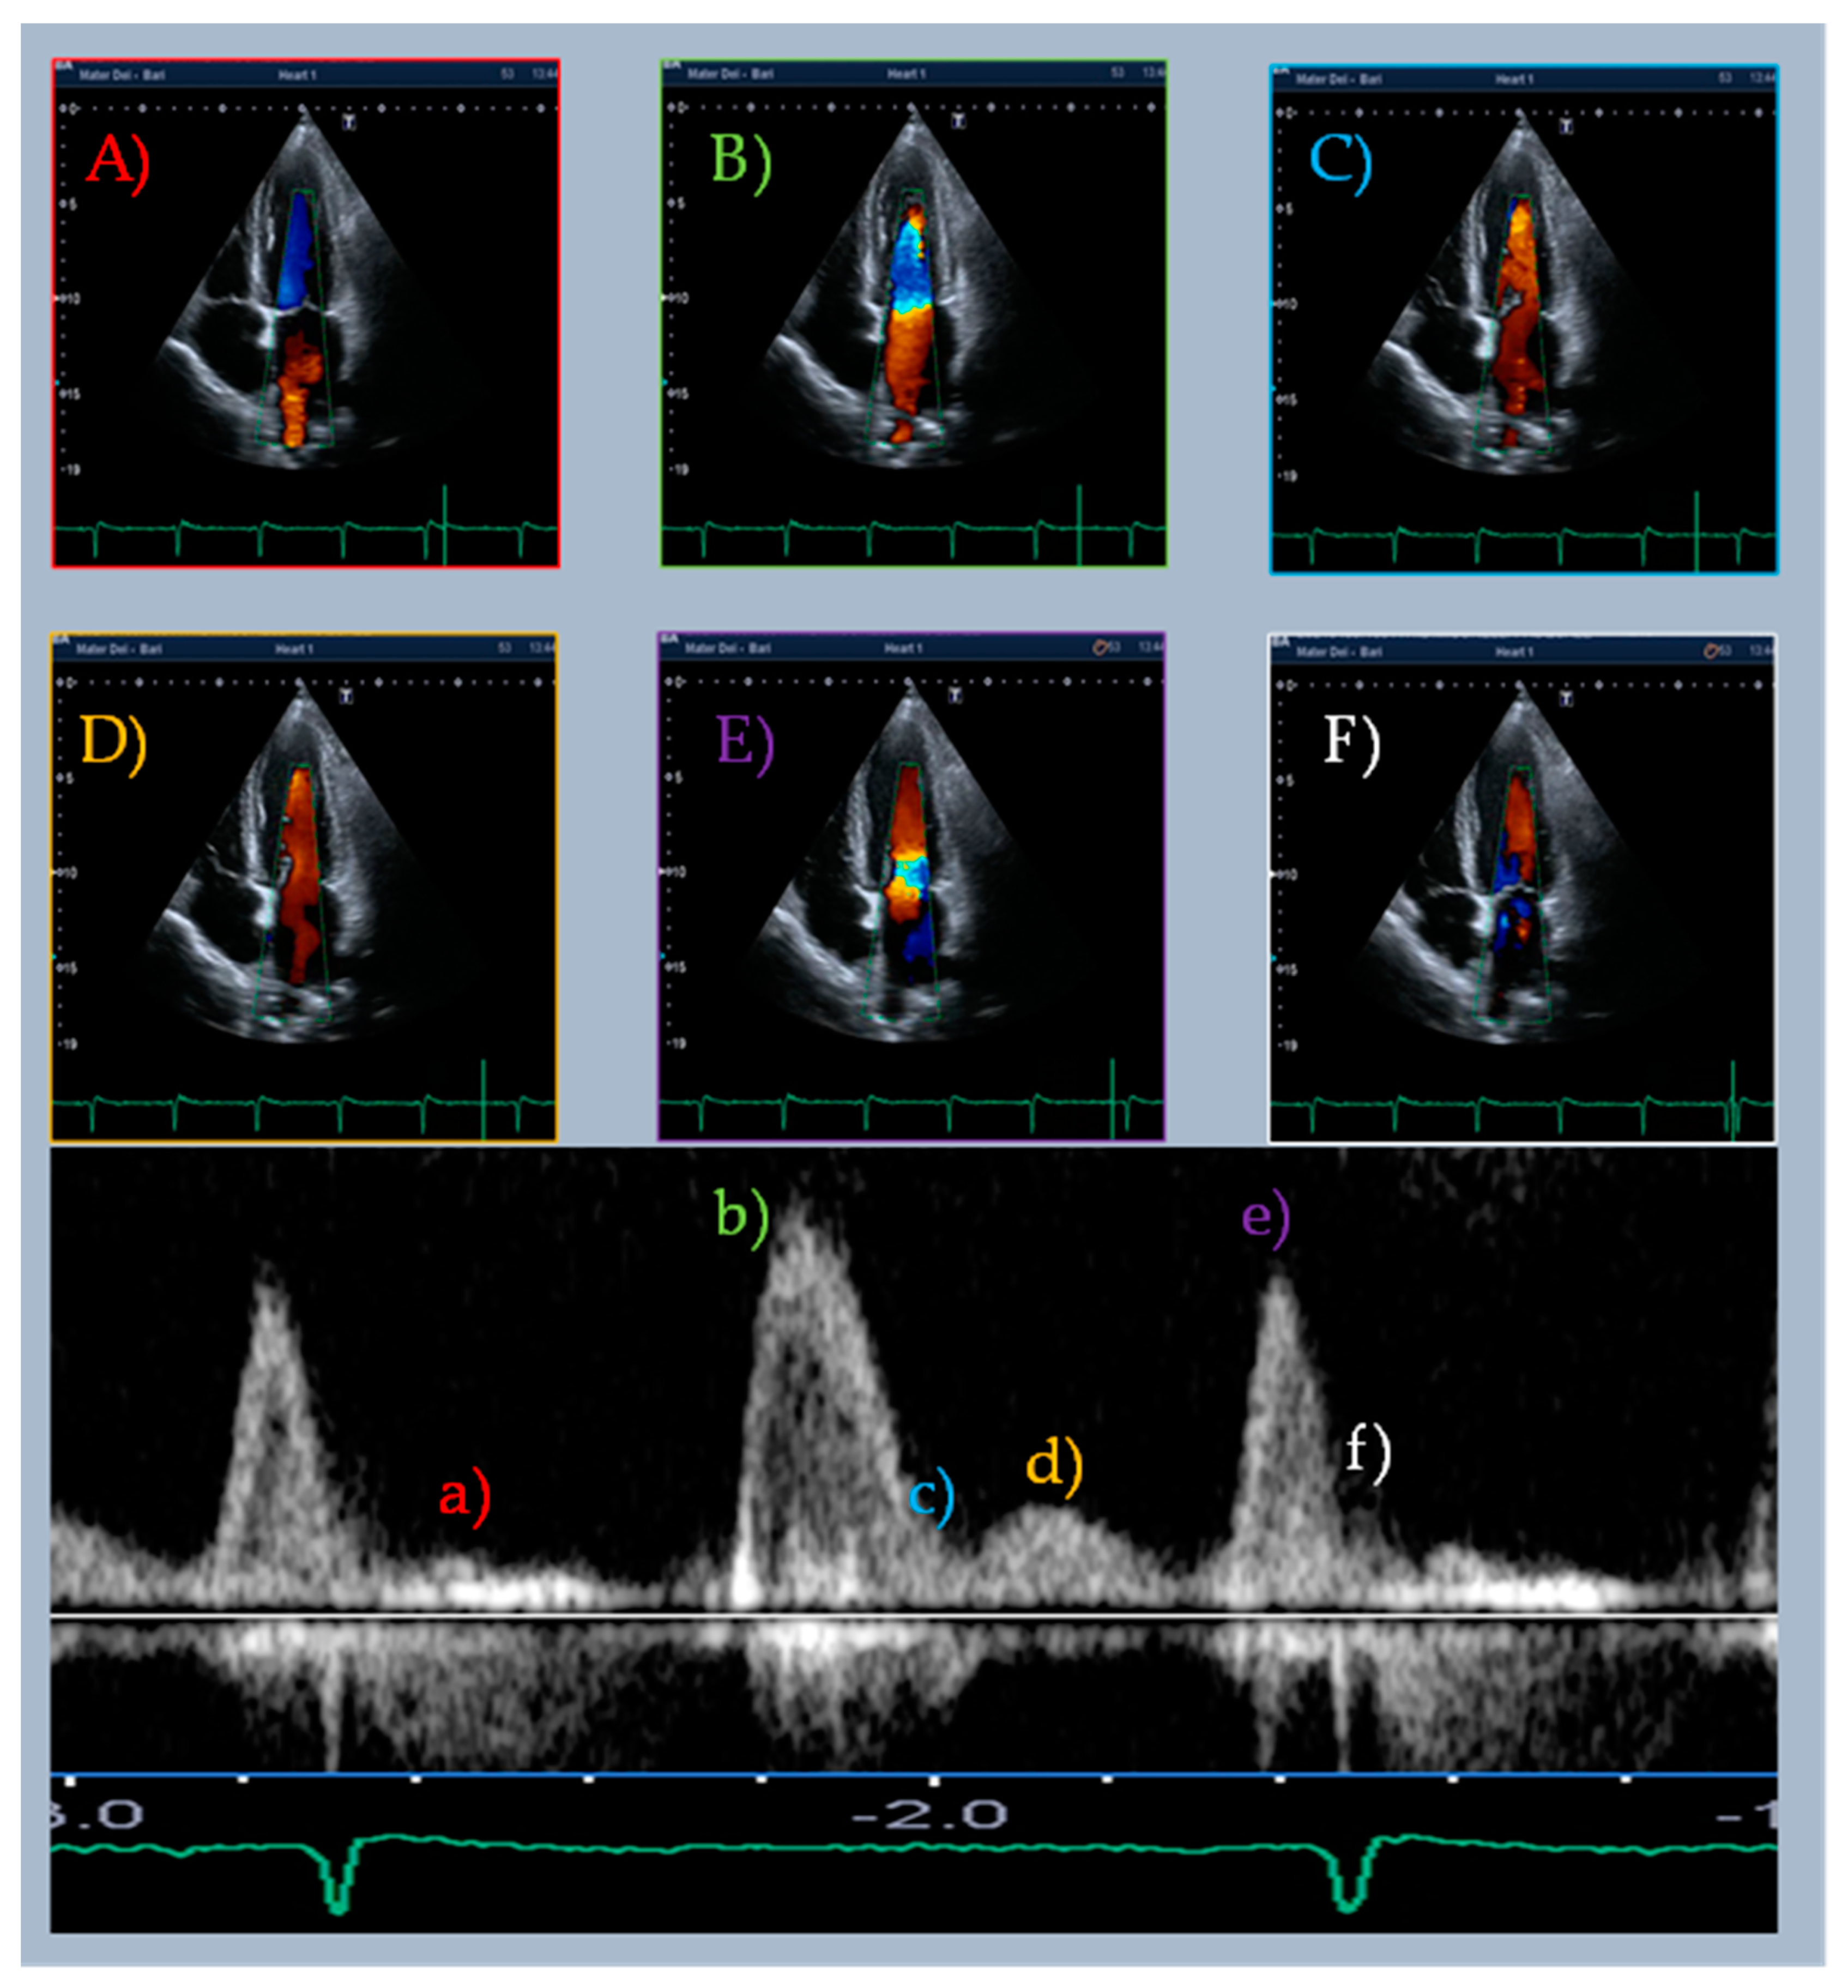

| Doppler-Parameters | Values | Chambers | Values | Strain and Strain Rate Parameters of LV and LA | Values | Time to Peak (ms) | %RR |

|---|---|---|---|---|---|---|---|

| E wave (cm/s) | 119.8 | IVS (mm) | 11 | GLS (%) | −16.7 | E wave | 49 |

| L wave (cm/s) | 32.3 | EDD (mm) | 53 | SR-irt (1/s) | 0.06 | G–E’ | 53 |

| A wave (cm/s) | 100.6 | EDV (mL/m2) | 63.9 | SR-E (1/s) | 0.69 | SR-E | 56 |

| E/A ratio | 1.2 | ESV (mL/m2) | 23.3 | E/SR-ivrt ratio (cm) | 1997 | G–L’ | 73 |

| E’ lat wave (cm/s) | 8.2 | LVEF (%) | 63 | E/SR-E ratio (cm) | 1.7 | L wave | 73 |

| L’ lat wave (cm/s) | 3.0 | LAVi (mL/m2) | 42.2 | SR-L (1/s) | 0.13 | SR-L | 75 |

| A’ lat wave (cm/s) | 13.8 | G–L’ (cm/s) | 0.59 | ||||

| E’ ivs wave (cm/s) | 8.1 | LA strain reservoir (%) | 34.2 | ||||

| L’ ivs wave (cm/s) | 2.2 | LA strain conduit (%) | 13.6 | ||||

| A’ ivs wave (cm/s) | 5.8 | LA strain contraction (%) | 20.5 | ||||

| E/E’ | 14.7 | aSR-E (1/s) | −0.77 | ||||

| IVRT (PW) (ms) | 61 | aSR-A (1/s) | −1.39 | ||||

| DT (ms) | 178 | (E/E’)/LA strain reservoir | 0.44 | ||||

| S/D wave ratio | <1 | ||||||

| TRV (m/s) | 2.8 |